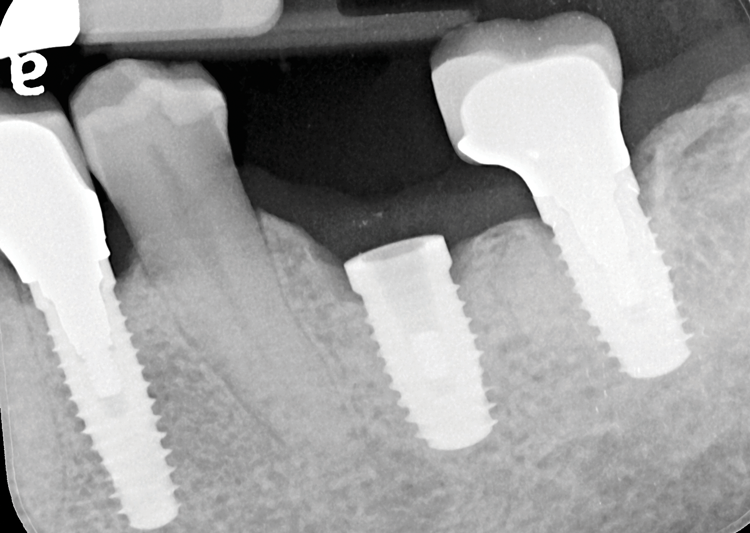

(3.) Periapical radiograph showing the extent and location of the prosthetic screw fragment.

Figure 3

A 61-year-old male patient presented with the chief complaint of a missing implant-supported crown. The patient's dental history revealed a habit of grinding and clenching, and signs of wear were clinically evident during the examination. Because the implant restoration was placed 7 years prior at another practice, and the manufacturer and model were not immediately available, a universal protocol would be required to attempt the rescue. The patient reported that the crown had been dislodged for many weeks. As a result, the soft tissue had grown over the implant, completely covering it (Figure 2). A preoperative periapical radiograph was taken to help visualize the location and size of the remaining fragment (Figure 3). In addition, an intraoral camera would be used during the procedure to view the internal aspect of the fixture and aid in the retrieval process.